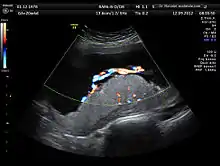

Two-dimensional (2D) is used to evaluate fetal structures, placenta, and amniotic fluid volume. Maternal pelvic organs are also evaluated. Views are obtained using an abdominal ultrasound probe, but a vaginal ultrasound probe may also be used to evaluate for placenta previa and cervical length. Three-dimensional (3D) ultrasound is not recommended for routine use during anomaly scan, but 3D ultrasound may be utilized to further evaluate suspected abnormalities in specific fetal features.[2]